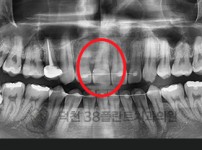

치료전후